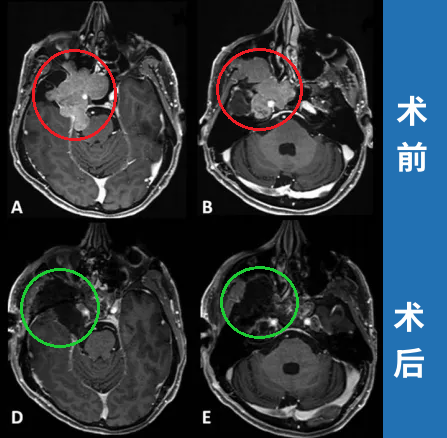

患者術(shù)前影像。(A)術(shù)前軸位T1加權(quán)釓增強(qiáng)磁共振成像(MRI),顯示腦膜瘤延伸至后顱窩、海綿竇、眼眶和蝶竇。(B)腫瘤延伸至中顱窩、翼腭窩和顳下窩。(C)術(shù)前軸位計算機(jī)斷層掃描(CT)顯示蝶骨大翼侵蝕和蝶竇受累。

術(shù)后MRI顯示腫瘤完全切除

手術(shù)順利完成,根據(jù)術(shù)前術(shù)后影像對比,患者腫瘤得到完全切除。

(A)術(shù)前軸向t1加權(quán)釓增強(qiáng)磁共振成像(MRI)顯示腦膜瘤延伸至后顱窩(PF)、海綿竇(CS)、眼眶和蝶竇(SS)。(B)腫瘤延伸至中窩、翼腭窩(PPF)和顳下窩(ITF)。(D, E)術(shù)后軸向t1加權(quán)釓增強(qiáng)MRI顯示腫瘤完全切除。

(C)術(shù)前軸向計算機(jī)斷層掃描(CT)顯示更大的蝶翼侵蝕和SS受累。(F)術(shù)后軸位CT掃描顯示用于閉合的脂肪移植物。

術(shù)后情況:術(shù)后患者的角膜炎在10天內(nèi)消退,V3感覺減退在2個月后得到好轉(zhuǎn)。